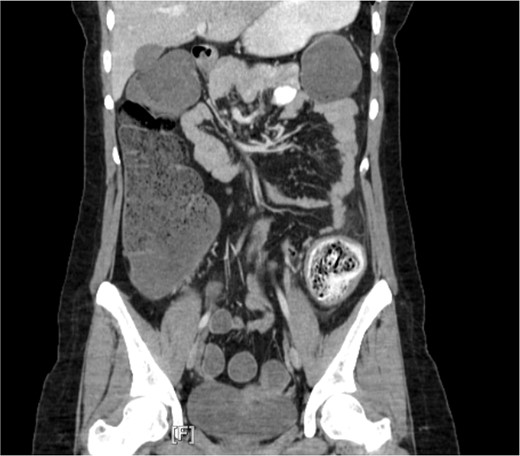

Subsequently, the patient underwent a series of three sigmoidoscopies on Day 2, 3, and 5 of her hospital stay (Fig. 2) after receiving polyethylene glycol prior to each intervention. During the first procedure, attempts at disimpaction of the fecaloma were made. Techniques used included saline lavage along with manual disimpaction with forceps and snares. Despite these efforts, disimpaction of the fecaloma was only minimally successful, leaving a significant amount of retained stool in the descending colon. The procedure was aborted, and the bowel regimen was continued along with the administration of a fleet enema; these measures brought only minimal relief. The following day, another sigmoidoscopy was performed, revealing a 35–40 cm fecaloma almost completely obstructing the bowel lumen with surrounding mild inflammation and ulceration. Attempts were made to dislodge the fecaloma using a net grasper, biopsy and snare, infusion of hydrogen peroxide diluted with saline, and an injection with mineral oil and an endoscopic retrograde cholangiopancreatography balloon. However, this attempt was unsuccessful, and a decision was made to repeat the sigmoidoscopy after giving the patient polyethylene glycol and fleet enemas for 2 days. Following this, the patient was able to pass more flatus and had a small watery bowel movement.

Direct visualization of the fecaloma causing colonic obstruction was obtained during the endoscopic intervention performed during hospital admission.